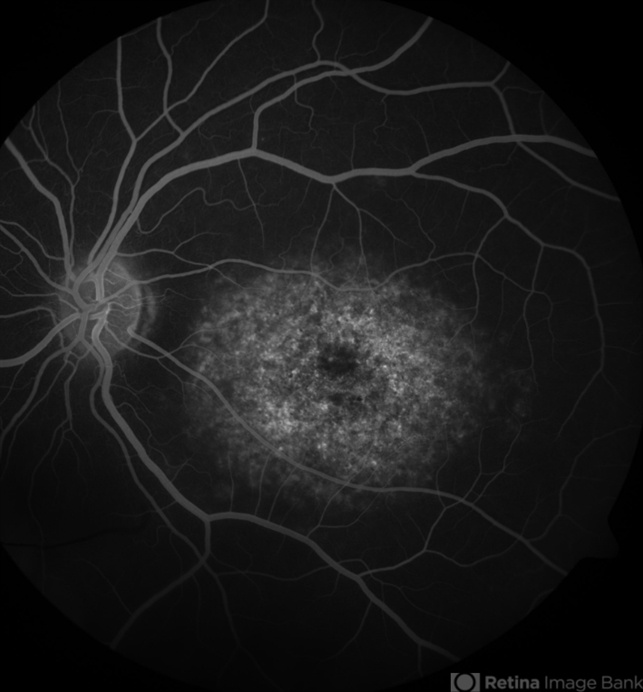

- Fluorescein angiogram of the left eye of a 48-year-old female with Stargardt's Disease. Note the dark choroid.